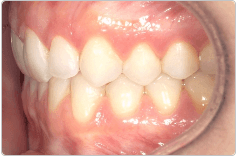

Diganosis: Moderate lower anterior crowding, square and narrow maxilla, rotated #19

Adjuncts: Attachments

Initial treatment

INTRAORAL